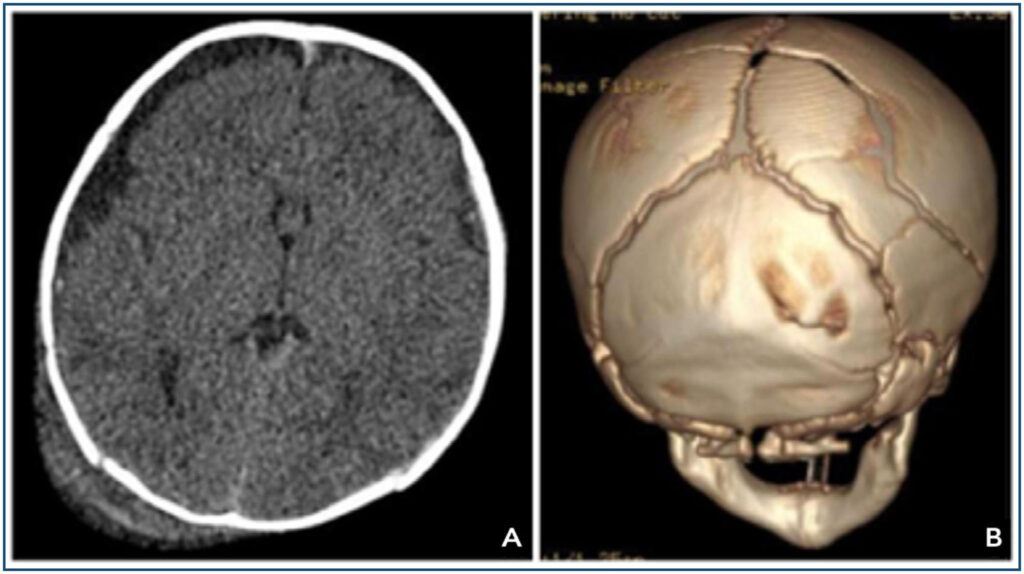

Crianças com a síndrome do bebê sacudido frequentemente apresentam hemorragias retinianas em várias camadas, com riscos de descolamento de retina, retinosquise macular e hemorragias vítreas, dependendo do impacto do trauma craniano. Danos permanentes à visão podem resultar de lesões diretas nos olhos ou no cérebro, sendo a última a principal causa de deficiência visual. Cicatrizes retinianas e atrofia do nervo óptico são geralmente irreversíveis e podem aparecer meses após a lesão. As constatações oftalmológicas podem oferecer dados diagnósticos significativos à equipe multidisciplinar, especialmente em situações em que há poucos indícios externos de abuso. O presente estudo relata o caso de uma criança com 2 meses de vida admitida em pronto-socorro oftalmológico e diagnosticado com síndrome do bebê sacudido.